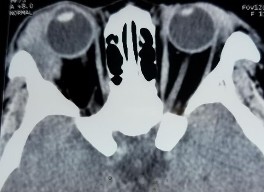

Bệnh nhân nữ, 32 tuổi, 2M: sưng nề mi góc ngoài Chẩn đoán: 2M: Quá sản lympho lành tính

Bệnh nhân sưng nề mi cách vào viện 1 tháng (A). Bệnh nhân đã điều trị nhiều đợt bằng kháng sinh, chống viêm đỡ nhưng tái phát. Hình ảnh cắt lớp vi tính có khối u góc trên ngoài ở cả hai mắt (C, D). Kết quả giải phẫu bệnh là quá sản lympho lành tính (E: HE x 100, F: HE x 200). Bệnh nhân đỡ sưng nề mi mắt rõ sau khi điều trị corticoid uống giảm liều (B).